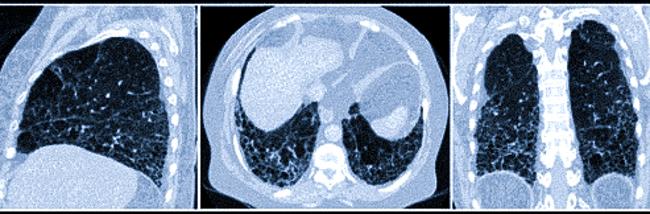

МРТ поможет точно установить причину боли.

Жапова Дарима Арсалановна, Москва, м. Киевская. Причины, по которым стоит сделать МРТ.

Магнитно-резонансная томография — это безопасный современный метод диагностики, который можно провести почти каждому.

На снимках МРТ можно увидеть позвонки, диски, мышцы, связки и нервные корешки, что делает возможным точную диагностику и определение самым оптимального плана лечения.

Магнитно-резонансную томографию. Она дает понять, есть ли повреждение связок и мышц, сдавление корешковы, выявить грыжу межпозвонкового диска